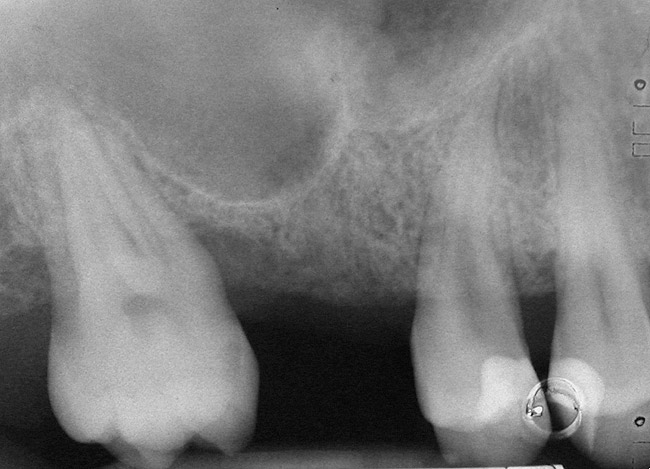

Case 3

A 53-year-old female was referred for evaluation of a fracture of tooth No. 24. The tooth had been treated endodontically 5 years prior. The radiograph revealed a complete fracture of the tooth involving the crown (Figure 12). Tooth extraction and immediate placement of a an implant that was 10 mm in length and 3.75 in diameter was planned.

At the time of surgery, the tooth was extracted without harvesting any mucosal flap because the implant site was prepared by means of a pilot drill bur (Figure 13) and alternating osteotomes (Figure 14A and Figure 14B). The implant was positioned and showed primary stability. The implant was loaded 2 days after surgery. Then, splinted PFM crowns supported by custom gold abutments were delivered. At 6 months posttreatment, the radiograph revealed no bone resorption and the clinical result was optimal (Figure 15A and Figure 15B).

Figure 15B Posttreatment radiograph, 6 months after the initial surgery.

Figure 15  Posttreatment radiograph, 6 months after the initial surgery.

Figure 15b